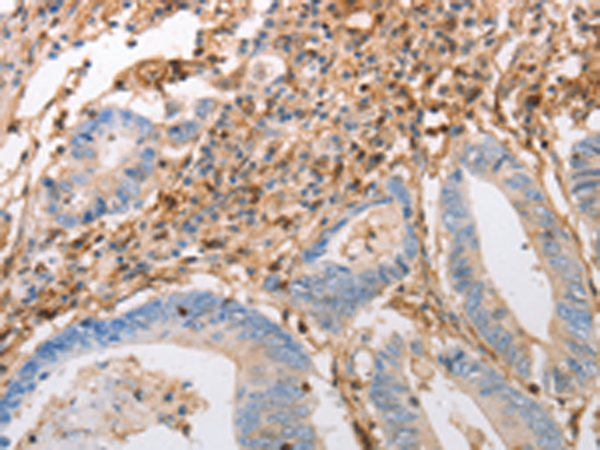

分类: 科研抗体货号: P11293别名: DLEC, HECL, BDCA2, CD303, CLECSF7, CLECSF11, PRO34150应用: IHC反应种属: Human